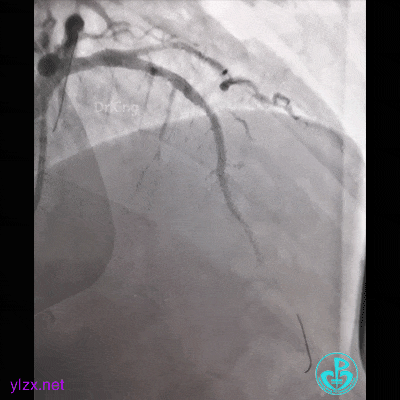

简单处理。

血运重建完成,胸痛缓解。生命体征平稳!